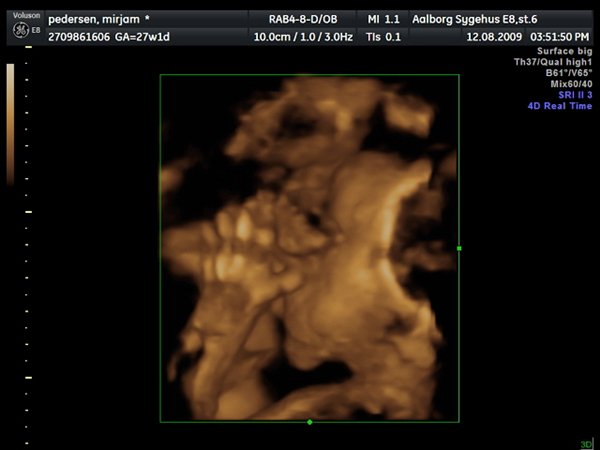

Så var jeg til 3D scanning, og det er en lille PRINSESSE

Hun var bestemt ikke samarbejds villig, vi skulle ihvertfald ikke bestemme hvordan hun sku ligge, så hun lå med hænderne oppe foran hovedet og somme tider med benene oppe foran os.. Så jeg fik rabat kom af med 800kr og han scannede mig ca 50 min. Han sagde hun vejede 990 gram

ups fik ikke billeder tilføjet

Vedhæftede fotos (klik for at se i fuld størrelse)